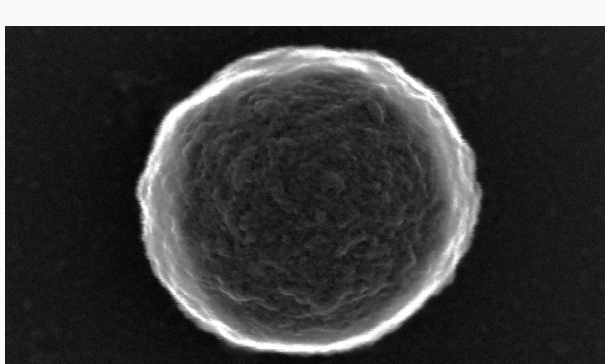

这种酶驱动微泡机器人由蛋白质外壳构成,具有良好的生物相容性,已广泛应用于医学成像领域。利用超声波搅拌技术,研究人员可快速、低成本地生产数千个相同的微泡。

通过化学修饰蛋白质外壳表面的胺基团,研究人员能够附着酶、药物和纳米颗粒,使微泡具备移动、环境感知和治疗功能。运动机制依赖于表面附着的脲酶,该酶与体内尿素反应产生化学副产物,形成推力推动机器人前进。